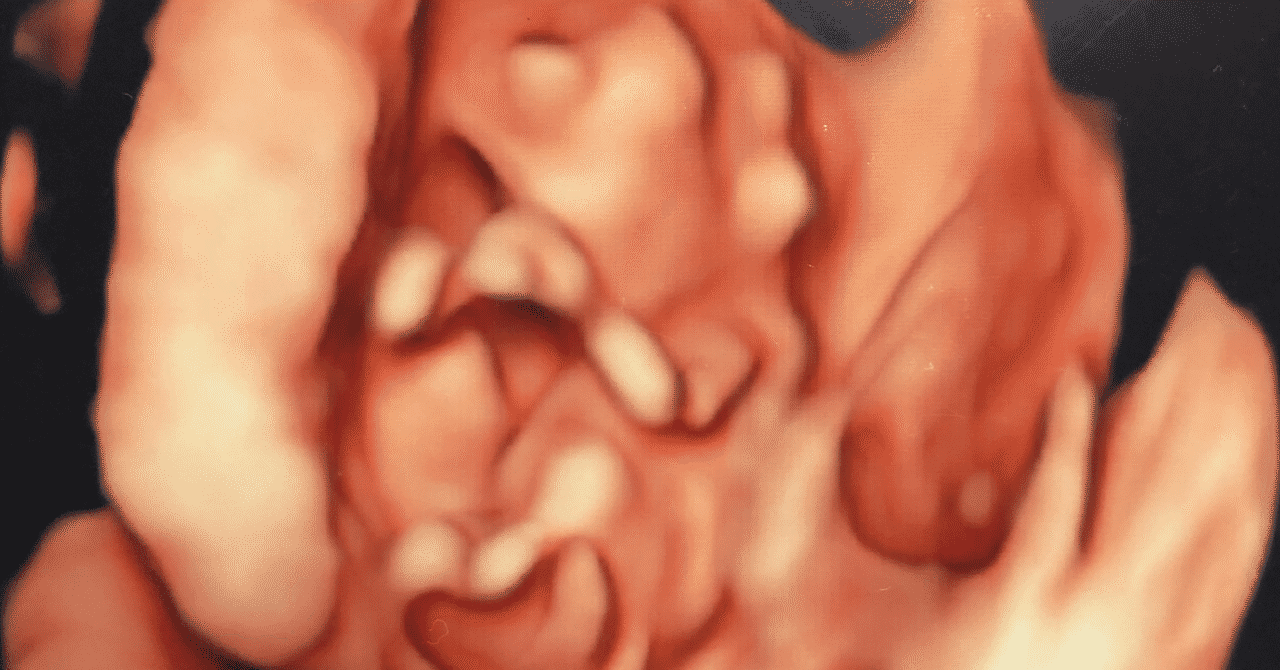

生まれてくる前の我が子の記念写真 超音波胎児スクリーニングでわかること 東京ベイ 浦安市川医療センター